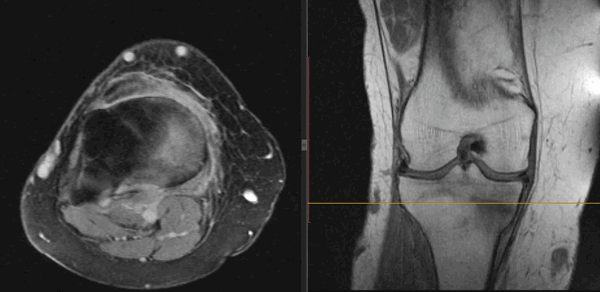

На Т2-ВИ в сагиттальной и корональной плоскостях определяется стресс-перелом дистальных отделов малоберцовой кости.

Перелом мыщелков большеберцовой кости - это нарушение целостности боковых отделов верхней части большеберцовой кости. Относится к числу внутрисуставных переломов. Может сопровождаться смещением или вдавлением отломков. Проявляется резкой болью, гемартрозом, выраженным ограничением движений в коленном суставе и нарушением опоры. Диагноз уточняют при помощи рентгенографии, реже используют КТ. Тактика лечения зависит от вида перелома, может использоваться гипсовая повязка, скелетное вытяжение и различные хирургические методики.

Перелом мыщелков большеберцовой кости - внутрисуставное повреждение боковых отделов верхнего эпифиза большеберцовой кости. Обычно сопровождается смещением или вдавлением участка суставной поверхности, поэтому характеризуется склонностью к развитию посттравматического артроза. Составляет примерно 13% от общего количества повреждений трубчатых костей, выявляется у людей любого возраста и пола, нередко встречается в составе политравмы. Переломы мыщелков могут сочетаться с повреждением связок коленного сустава, повреждениями менисков, переломами малоберцовой кости и межмыщелкового возвышения.

- Рентгенография коленного сустава. Является основным методом инструментальной диагностики. Рентгеновские снимки выполняют в двух проекциях. В абсолютном большинстве случаев это позволят достоверно установить не только факт наличия перелома мыщелков, но и характер смещения отломков.

- Другие визуализационные методики. При неоднозначных результатах рентгенографии пациента направляют на КТ коленного сустава. При подозрении на сопутствующее повреждение мягкотканных структур (связок или менисков) назначают МРТ коленного сустава.